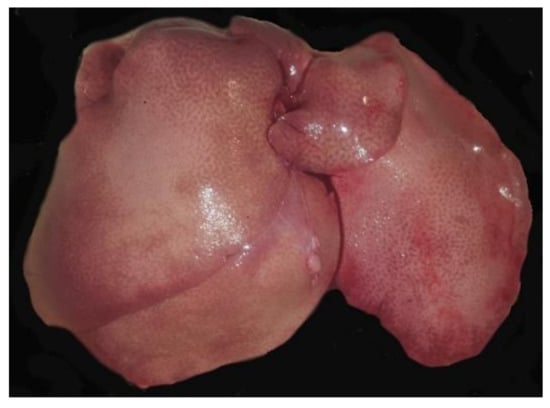

The liver of case 4 (dosed with 3 mmol/kg of CHB and euthanised 8 h PD) was extremely friable, and that of case 13 (dosed with 0.25 mmol/kg CHEB and euthanised at 96 h PD) was paler than normal with a prominent lobular pattern (Figure 3). In case 9 (dosed with 3 mmol/kg of CHEB and euthanised at 2.5 h PD), blood was noted in the stomach.

Figure 3. The liver of case 13 (dosed with 0.25 mmol/kg CHEB and euthanised at 96 h PD) was paler than normal with a prominent lobular pattern.

The periportal necrosis seen in case 2, which received a single dose of 1 mmol/kg CHB and was euthanised at 48 h PD (Figure 5B and Figure 6A), was strikingly similar to that seen in case 4 (Figure 5A and Figure 4B). Severe periportal coagulation necrosis was also seen in case 13, which received a single dose of 0.25 mmol/kg of CHEB (Figure 3 and Figure 5C) and was euthanised at 96 h PD whilst appearing clinically normal (HES = 0). The liver of case 13 also showed moderate hyperplasia of bile ducts, which sometimes formed bridges between adjacent portal tracts (Figure 5C). Massive hepatic necrosis, characterised by diffuse hepatocellular karyopyknosis with scattered cells showing karyolysis and apoptotic bodies, was present in case 8, which received a single dose of 1 mmol CHEB (Figure 6B) and was found dead at 23 h PD, despite having an HES of 0 when observed two hours prior. Single doses of 0.5 mmol/kg (case 10), 0.375 mmol/kg (case 11), and 0.3125 mmol/kg (case 12) CHEB were all severely hepatotoxic, resulting in high HES scores necessitating euthanasia or death (case 12) by 18 h PD. Liver lesions in these three cases were similar to those of case 8. A mild mononuclear inflammatory infiltrate, together with isolated heterophils and apoptotic fragments, was present in portal tracts (Figure 6C). In addition to the changes already described, small numbers of heterophils were scattered throughout the parenchyma and portal tracts of cases 4 (CHB 3 mmol/kg) and 8–13 (CHEB 0.25 mmol/kg–3 mmol/kg) (Figure 7A). Heterophils were frequently located inside lysed hepatocytes, a phenomenon known as emperipolesis (Figure 7A).